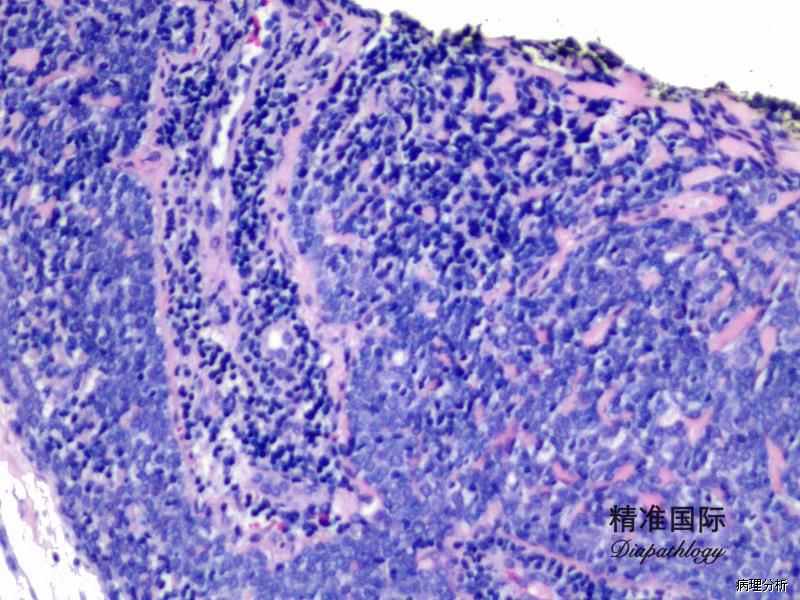

瘤体位于真皮深层,由多个或单个小叶组成,与表皮不相连,可有不完整的包膜;

小叶周边细胞体积小,基底细胞样,胞浆少,核圆形,深染;小叶中央细胞体积大,核淡染,苍白,胞浆嗜酸性;

间质可见玻璃样变物,有时可见淋巴细胞浸润;